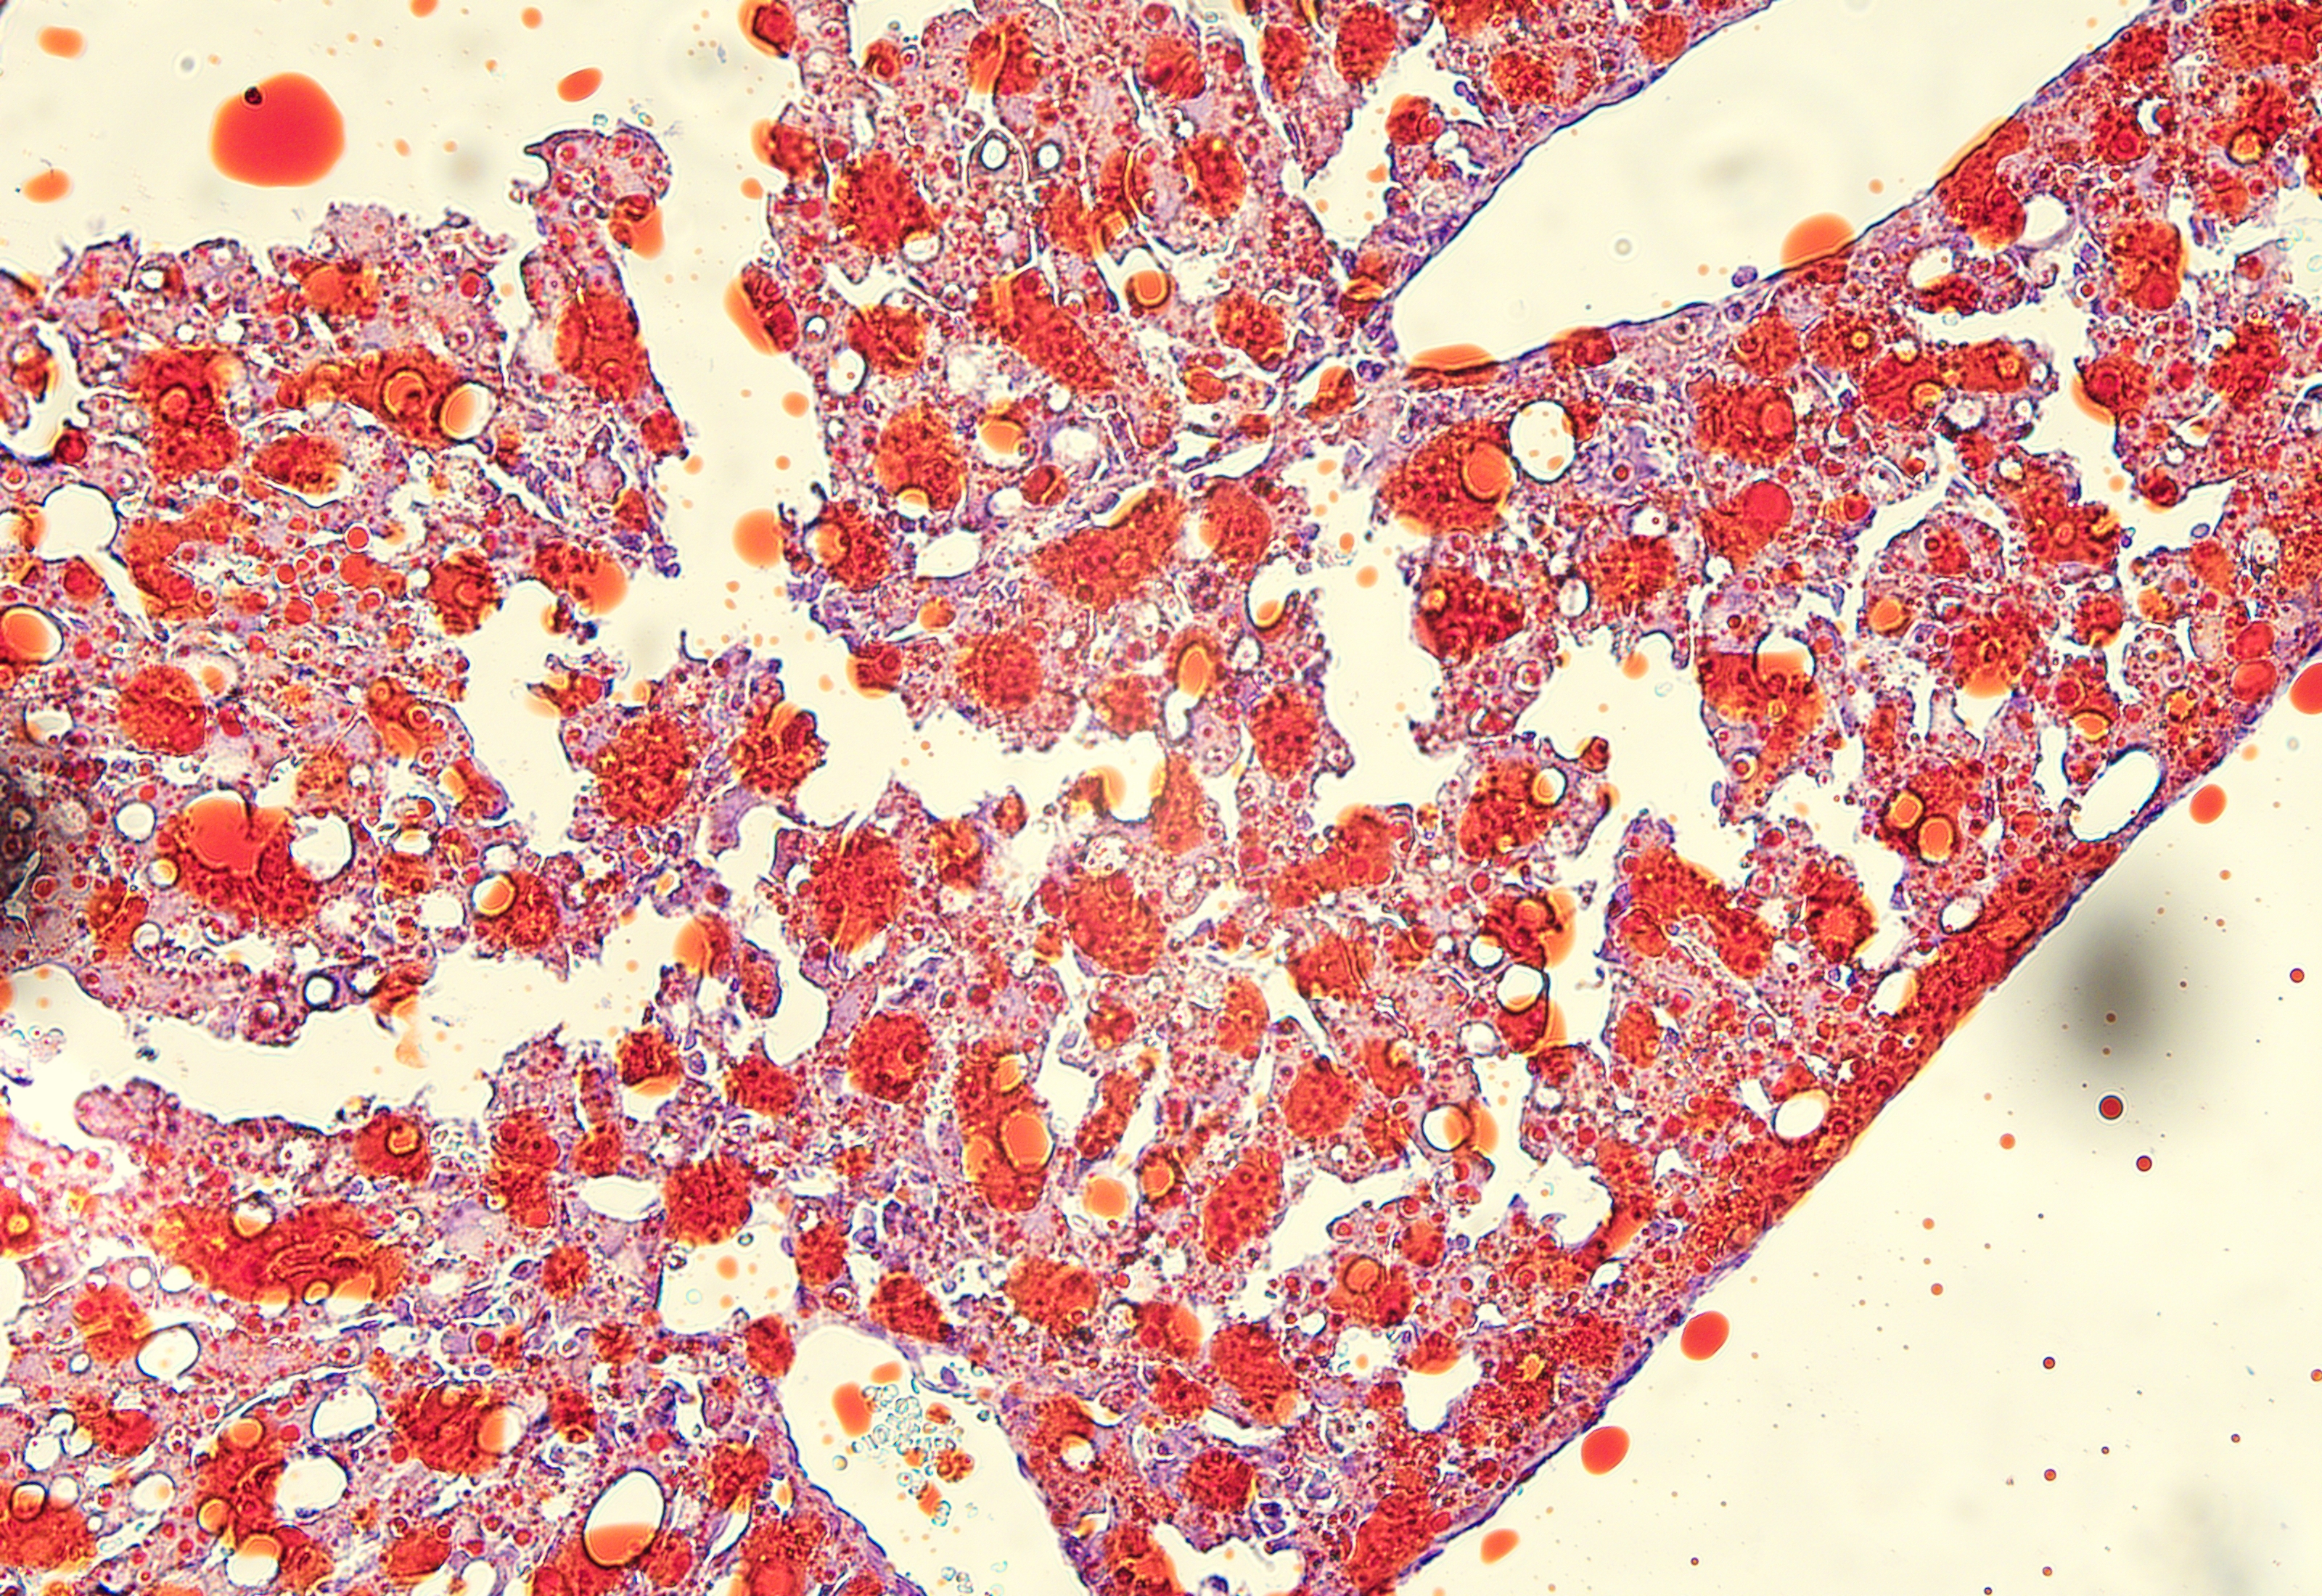

油红O染色

油红O脂肪染色法是指在日常病理诊断和科研工作中为了显示组织内的脂肪常采用油红O进行染色的方法,油红O为脂溶性染料,在脂肪内能高度溶解,可特异性的使组织内甘油三酯等中性脂肪着色。

脂肪肝模型动物的肝脏油红 冰冻切片染色